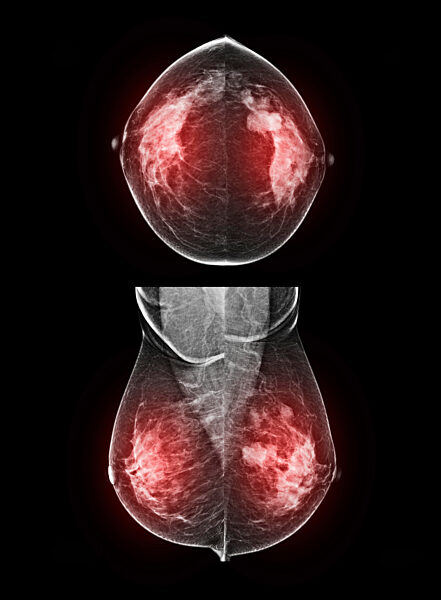

01.01.1000 - Coloured breast X-ray (mammogram) showing a BI-RADS (Breast Imaging Reporting and Data System) categorisation score of 5. A BI-RADS score of 5 is highly suggestive of a malignant (...

560491748

01.01.1000 - Coloured breast X-ray (mammogram) showing a BI-RADS (Breast Imaging Reporting and Data System) categorisation score of 5. A BI-RADS score of 5 is highly suggestive of a malignant (...

560492261